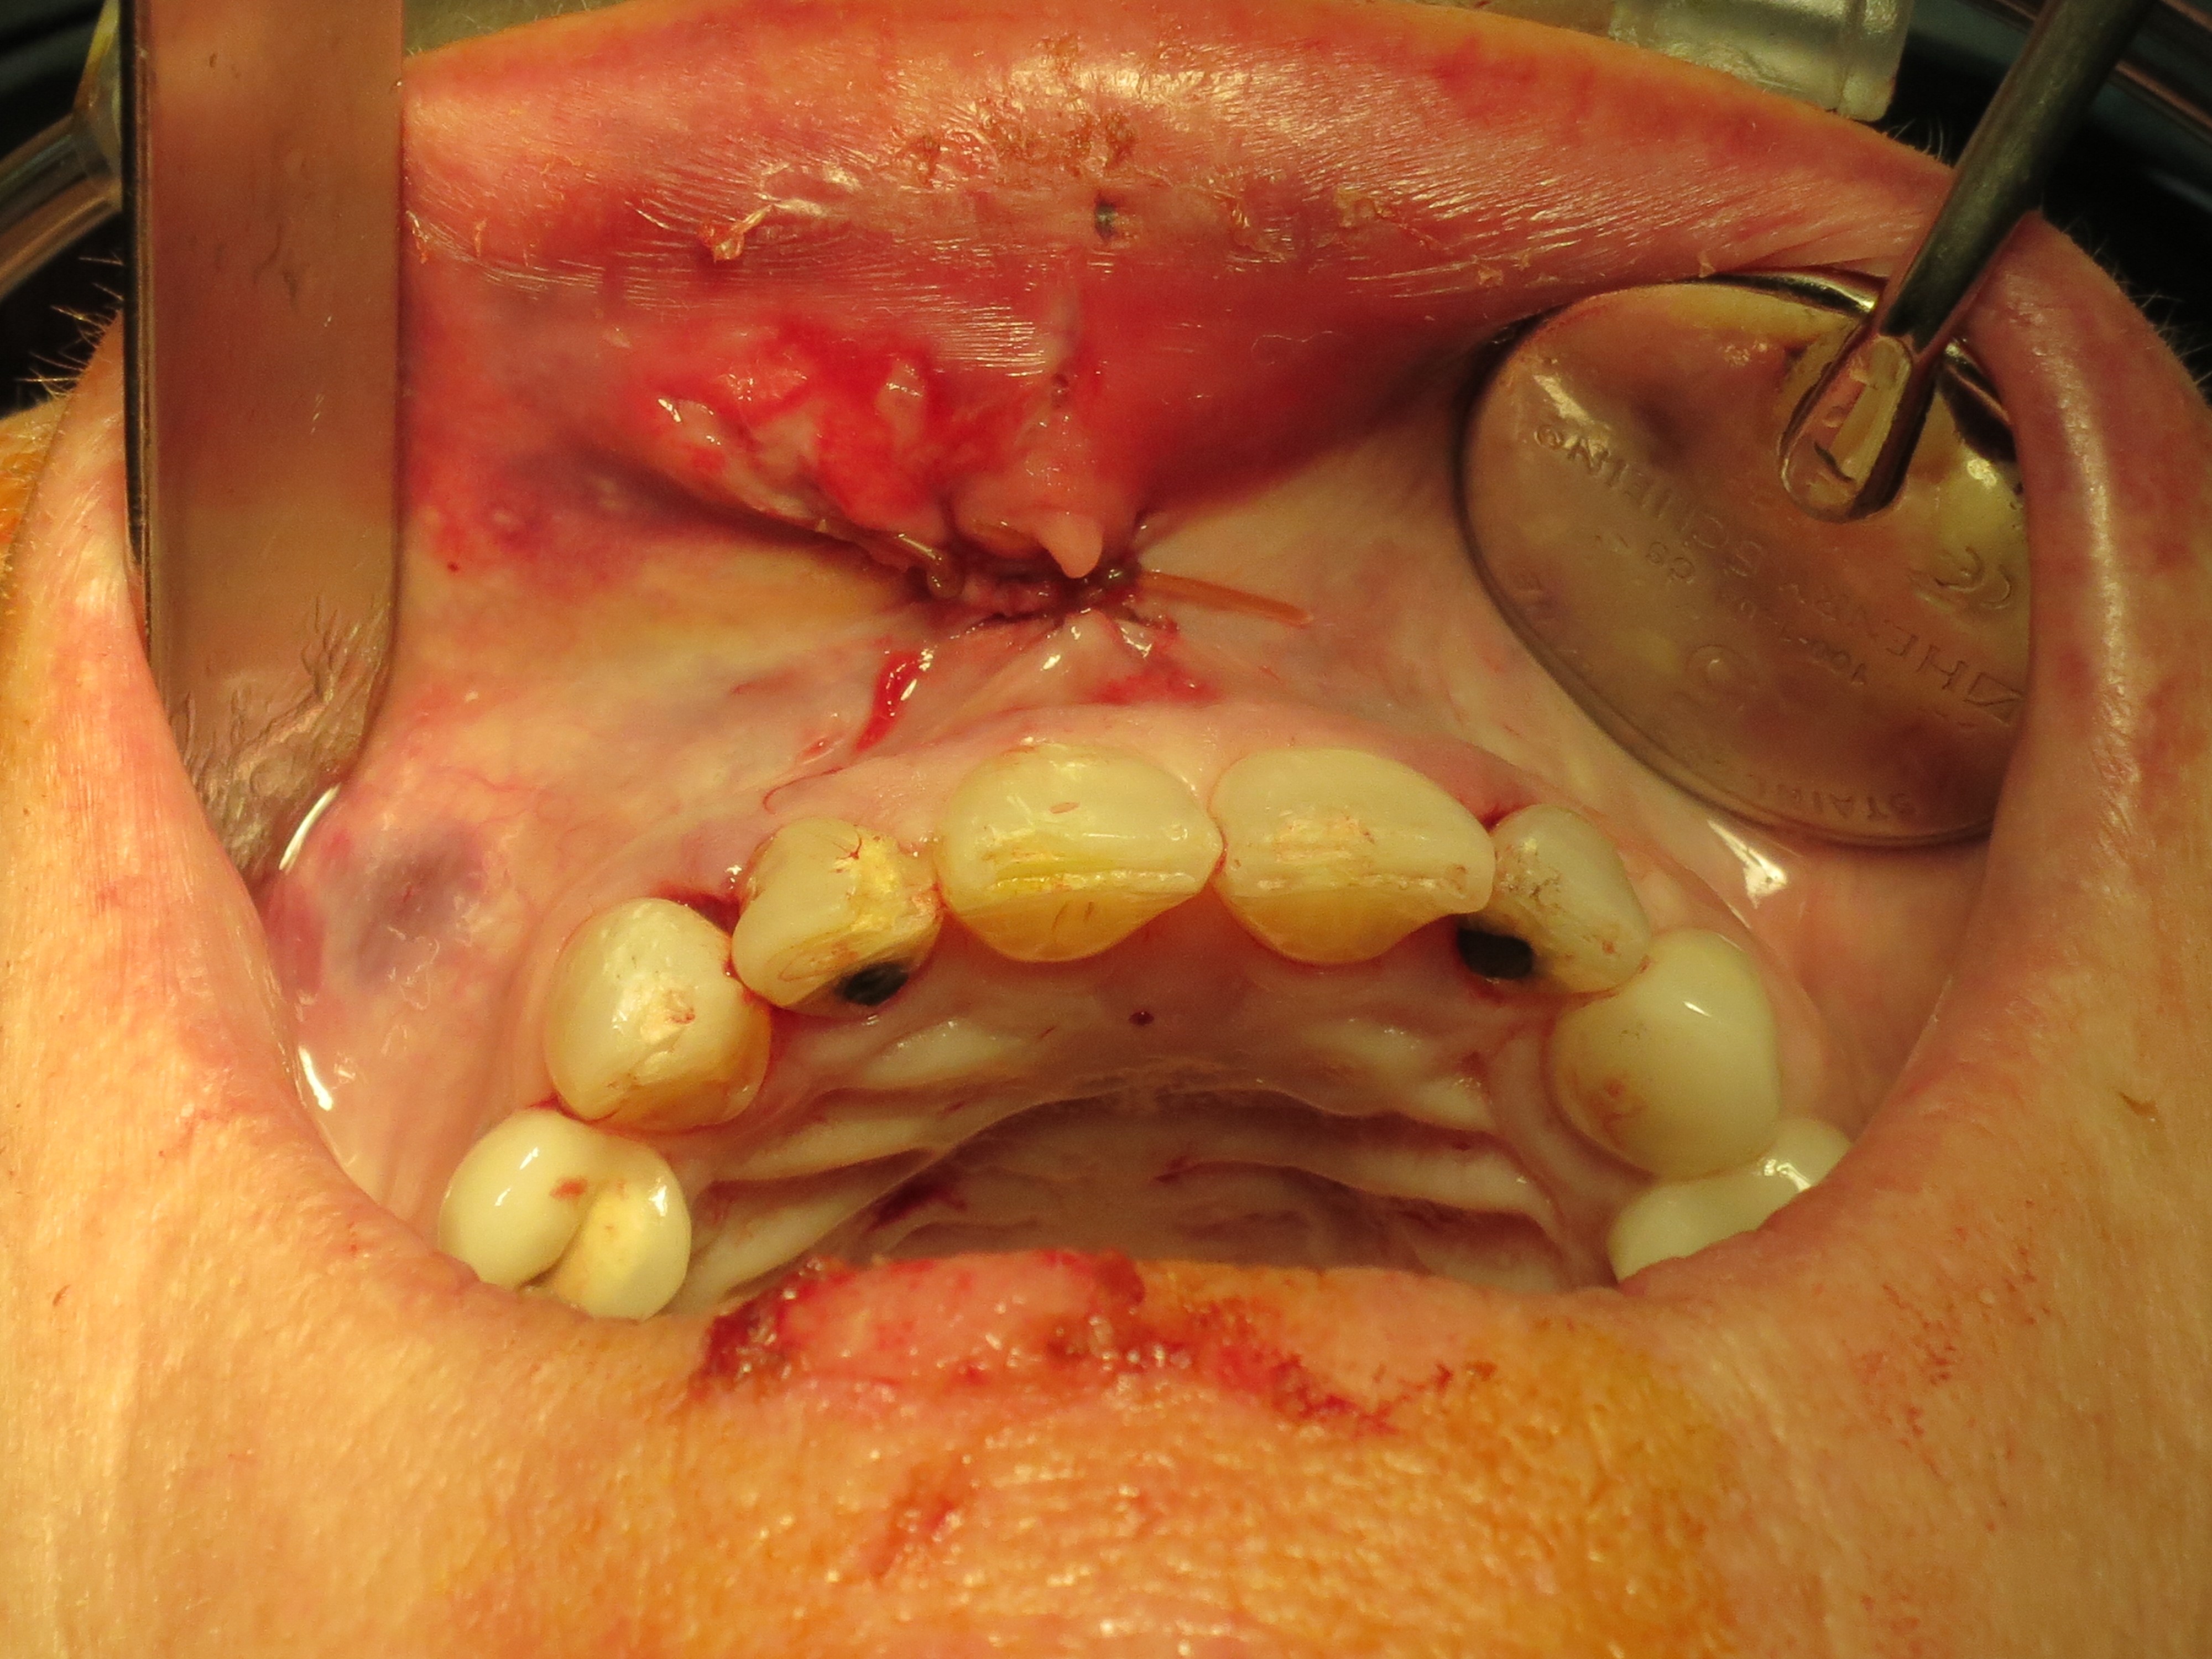

On an intra-oral examination, her teeth present with a “step deformity”, where the 3 front teeth do not line up with the adjacent teeth.

There is an internal laceration that was missed at the hospital. Even though the laceration on the outside of the face was closed with sutures, this was a “through and through” laceration that went from the outside intraorally.

She was immediately brought back to the operating suite, IV sedated in order to “reset” her occlusion and “pop” the alveolar fracture + the teeth back into it original location. The intraoral incision was cleansed and closed with resorbable sutures.